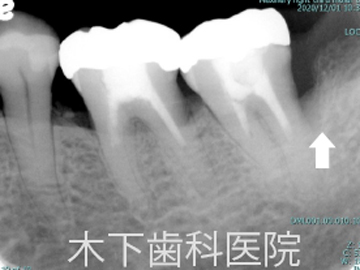

歯周外科術前

リグロスを用いた歯周組織再生療法症例

術前